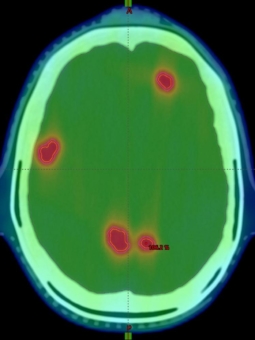

Simultanbestrahlung von Hirnmetastasen: Studie soll wichtige Grundlagen schaffen

Posted on 19. Januar 202219. Januar 2022 by Firma Universitätsklinikum Freiburg

Entwicklungen der letzten Jahre ermöglichen heutzutage die hochpräzise Bestrahlung sehr kleiner Tumoren. Besonders profitieren davon Patient*innen mit Hirnmetastasen. Mittlerweile können sogar mehr... Read More